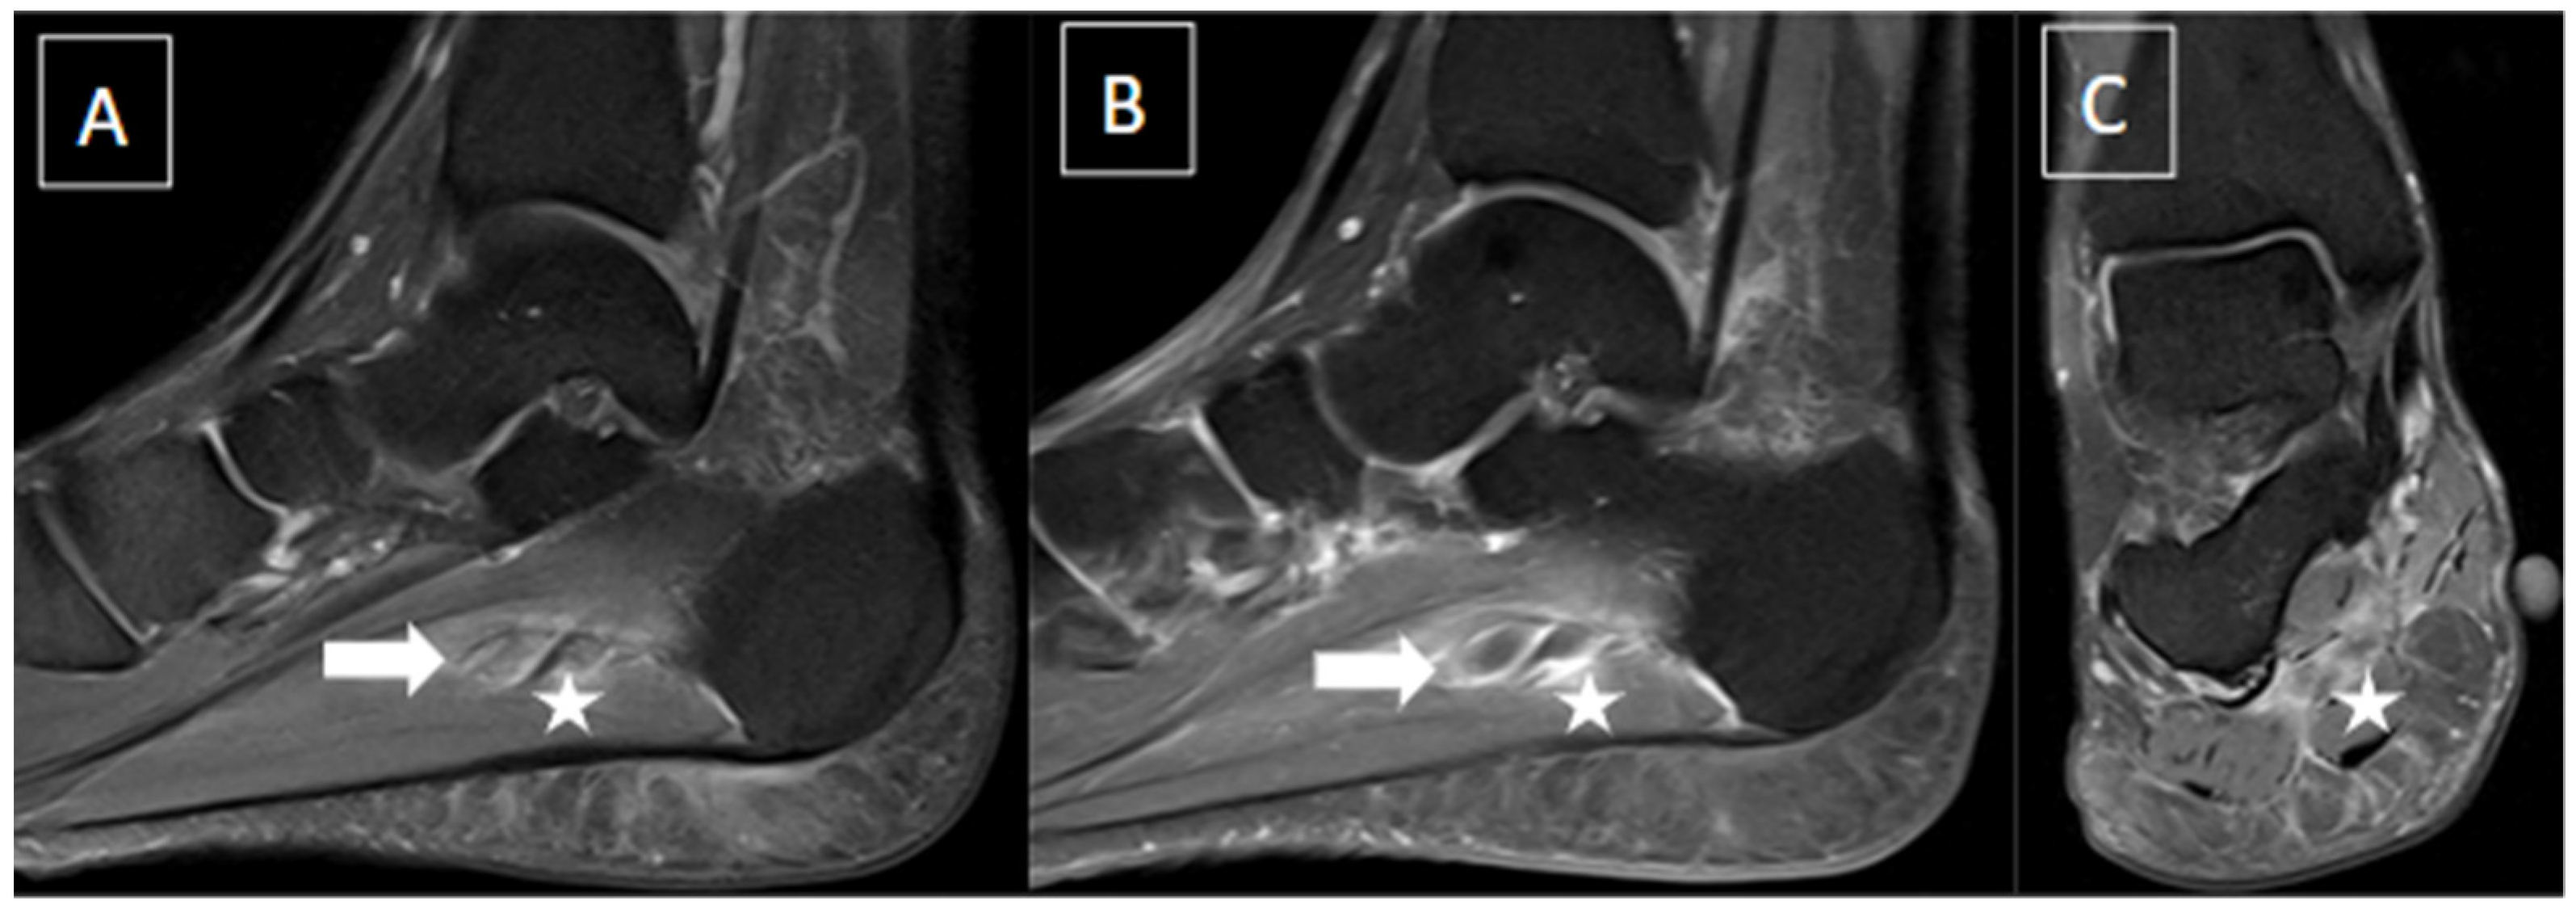

| Perivascular edema and enhancement Muscle edema Intraluminal signal change Venous enlargement Presence of collateral veins Venous filling defects (post-gadolinium injection) | Local tenderness Loss of compressibility Venous enlargement Intraluminal content Perivascular edema | Local tenderness Loss of flow Filling defects |